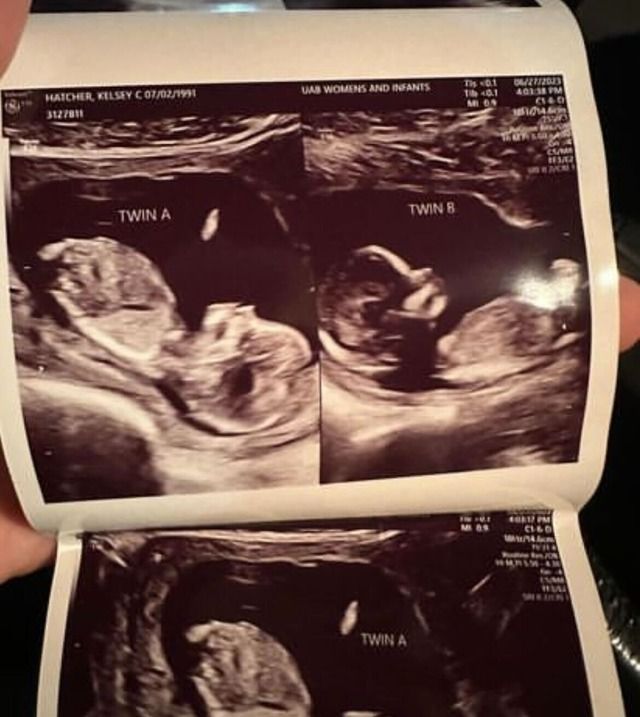

Kelsey Hatcher, 32 from Alabama in the United States, was born with two uteruses is now pregnant in both.

The couple was even more surprised to learn at Kelsey Hatcher’s eight-week ultrasound appointment that she was expecting two babies, each in a separate uterus.

The mother-of-three has known about her rare condition, called uterus didelphys, since she was 17. However, she never imagined she would carry a baby in both at the same time.

Though the babies aren’t sharing a uterus, according to Dr. Shweta Patel, the OB-GYN looking after Kelsey said the babies are considered fraternal twins.